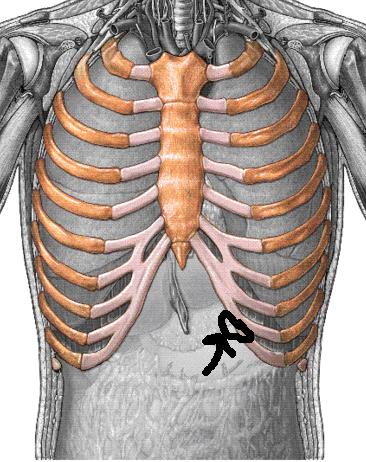

늑골이라고 명명되며 12쌍을 이루고 있는 갈비뼈는 내부의 심장, 폐, 간 등 주요 장기를 막아주는 역할은 물론 몸의 형태를 계속하고 정상적인 생활을 하는 데 있어 굉장히 귀중한 인체 부위에 부합됩니다.

오른쪽 갈비뼈 아래 통증 주요 원인 12가지